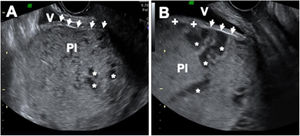

Diagnóstico ecográfico de placenta previa con acretismo. Se objetiva placenta previa insertada en la cara anterior del segmento inferior uterino (la localización más frecuente). El miometrio está muy adelgazado, llegando a ser indetectable. La «línea vesical», que marca la separación entre las serosas uterina y vesical, aparece como una línea ecogénica (flechas), que llega a desaparecer en algún punto (+). Este signo debe hacernos sospechar una placenta percreta Pl: placenta; V: vejiga; *: lagunas vasculares.

Las anomalías de la implantación placentaria son causa de alta morbimortalidad maternal y neonatal por la hemorragia masiva que puede producirse durante el parto. El espectro de la placenta acreta (PAS) acontece cuando la placenta crece profundamente en la pared uterina pudiendo invadir el miometrio o incluso los tejidos, vasos y órganos pélvicos circundantes1. El Panel de Consenso de Expertos de FIGO ha desarrollado una nueva clasificación del PAS dividiéndola en 3 grados según la profundidad de la invasión. En el grado 1 (placenta adherente o creta), las vellosidades se insertan directamente en el miometrio; en el grado 2 (íncreta), las vellosidades penetran en el interior del miometrio. En el grado 3 (pércreta), las vellosidades alcanzan la serosa peritoneal e incluso invaden órganos vecinos (fig. 1). La incidencia de estas anomalías ha aumentado en los últimos años debido al aumento paralelo de la tasa de cesáreas y se han convertido en una complicación obstétrica cada vez más común2.